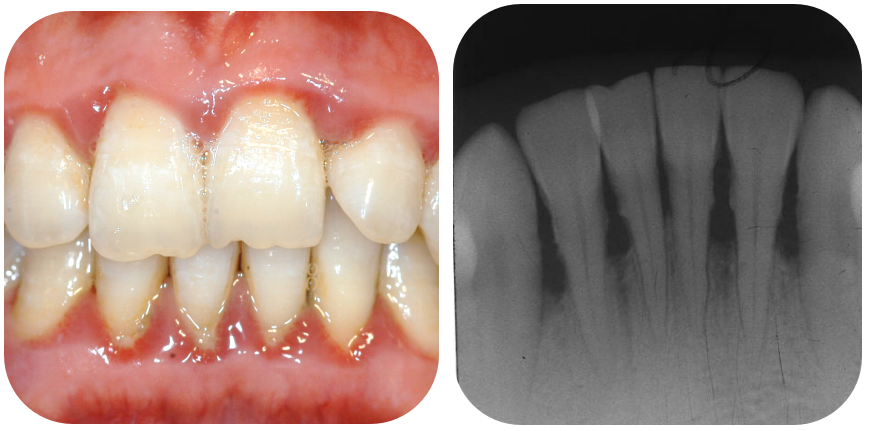

早期牙周炎:牙龈出血、口臭,易被误认为“上火”。此时牙槽骨轻度吸收,骨高度降低。可经过牙周基础治疗(洁治、龈下刮治等)控制炎症,及时止损。

中期牙周炎:牙龈萎缩、牙缝变大,常误以为是“自然衰老”。此时牙槽骨已明显吸收,但牙齿松动可能仍不明显。如牙周基础治疗效果一般,通常会建议牙周手术治疗。